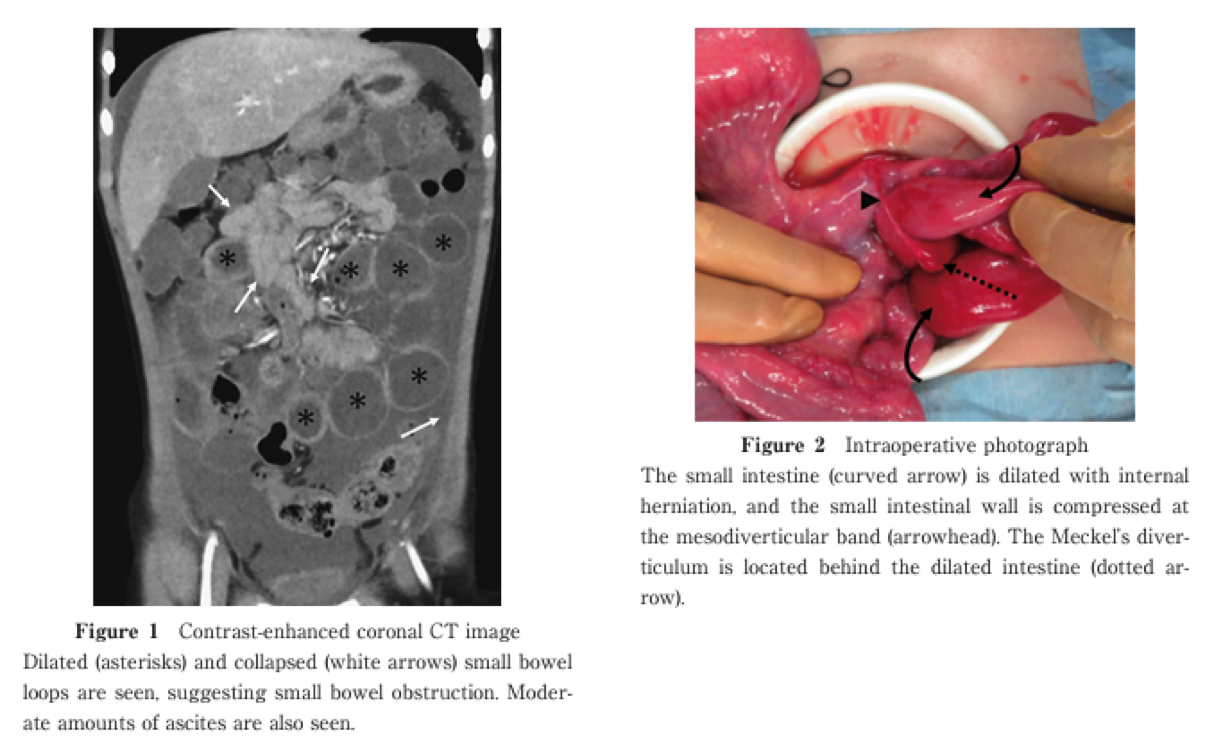

CT Findings of Complex Small Bowel Obstruction Due to Internal Hernia Caused by Meckel’s Diverticulum with Mesodiverticular Band

Mariko Kumazawa et al.

Published online : March 27 , 2025